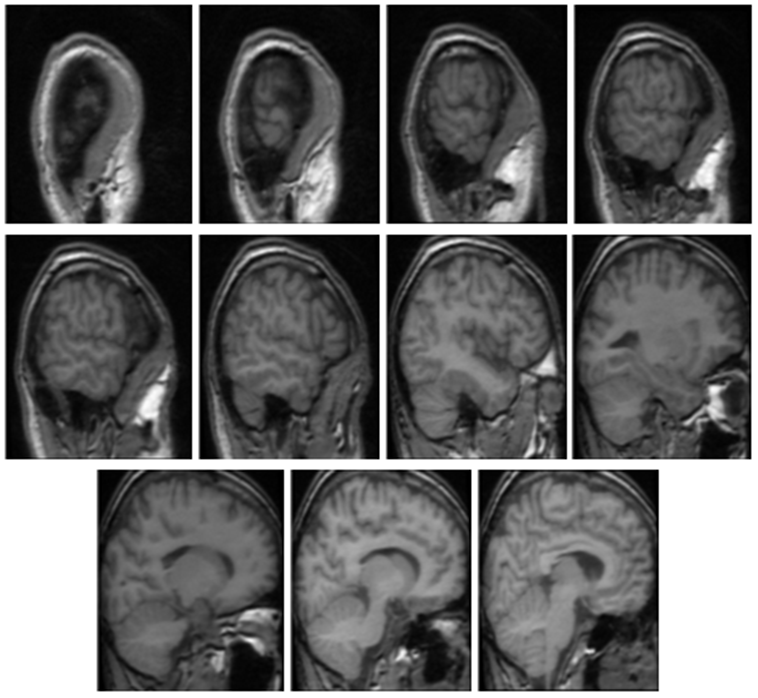

In the first stage, we divide sagittal slices into several groups by initial analysis of brain regions’ shapes. We categorize slices into three groups based on their general shape, entitled Group I, II, and III. In Figure 2, we illustrate a few slices in each groups. It is clear that the brain region in Group I is quite small compared to the image size. Meanwhile, the brain areas in Group II and Group III are relatively large, and the brain regions in Group III extend out at the lower-left corner of images. For taking advantage of the symmetry of the human brain across the sagittal plane, we assign the corresponding group of each slice by the following order: Group I, Group II, Group III, Group II, and Group I. Figure 3 depicts how three groups distribute throughout the sagittal axis.

Refer to caption

Figure 2: Typical appearances of each group. Top row: group I; middle row: group II; bottom row: group III.